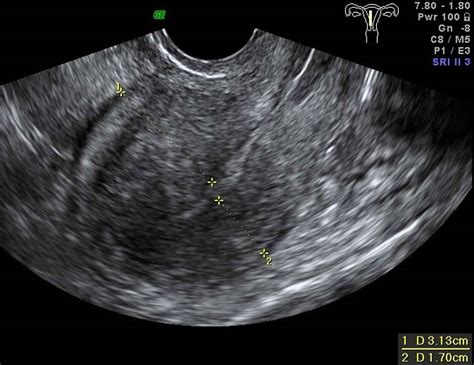

• Transvaginal Ultrasound: The first line of defense. It can often reveal the characteristic "globular" enlargement of the uterus and the "venetian blind" shadowing pattern associated with adenomyosis.